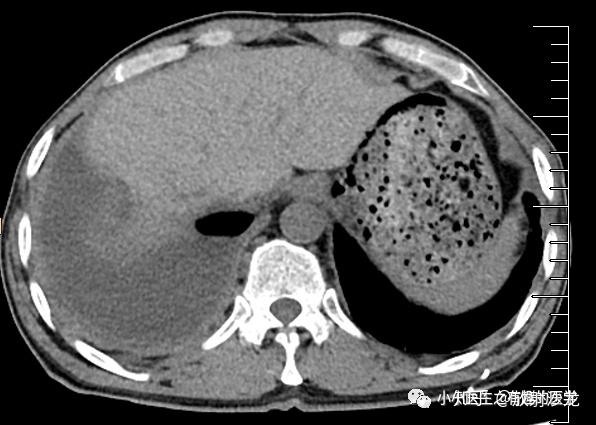

游离性胸腔积液